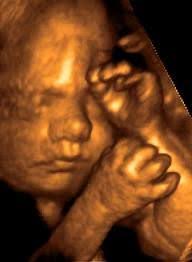

Bebeğinizin boyu 29 cm, ağırlığı ise 500 gramdır.

Bebeğinizin göz hareketleri hızlanmıştır. Derisi pembeden kırmızıya doğru bir renktedir. Akciğerlerdeki küçük hava keseciklerinin duvarından bu keseciklerin gelişmesini ve olgunlaşmasını sağlayan sürfaktan salgılanmaya başlar. Sürfaktan prematüre bebeklerde çok az miktarda üretildiği için solunum sıkıntısı yaşarlar.

Büyüdükçe gelişen ve sertleşen kemikleri ve güçlenen kasları ile bebeğinizin hareketlerini daha güçlü hissedersiniz. Bazı hareketlerini karnınızdan takip edebilir hatta tekmeleme, dönme ve gerilme şeklindeki değişik hareketlerini ayırt edebilirsiniz. Her bebeğin kendine özgü bir hareket etme alışkanlığı geliştiği için bazı bebekler daha az bazı bebekler daha fazla hareket edebilirler.